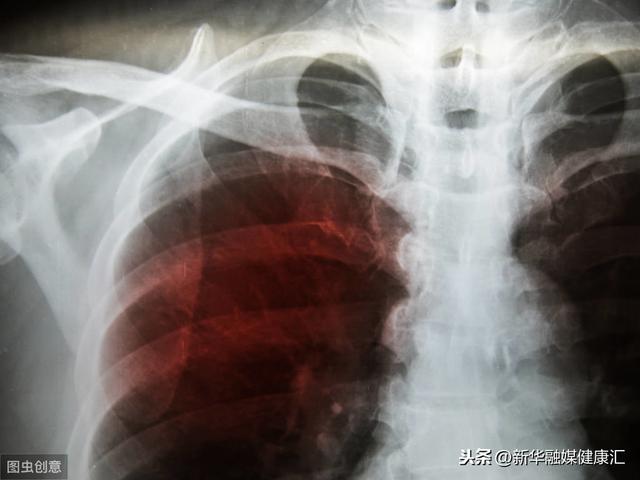

30多年结核病史 最终肺全毁损了 结核菌有多厉害 全身都能侵犯 快资讯

30多年结核病史 最终肺全毁损了 结核菌有多厉害 全身都能侵犯 知乎